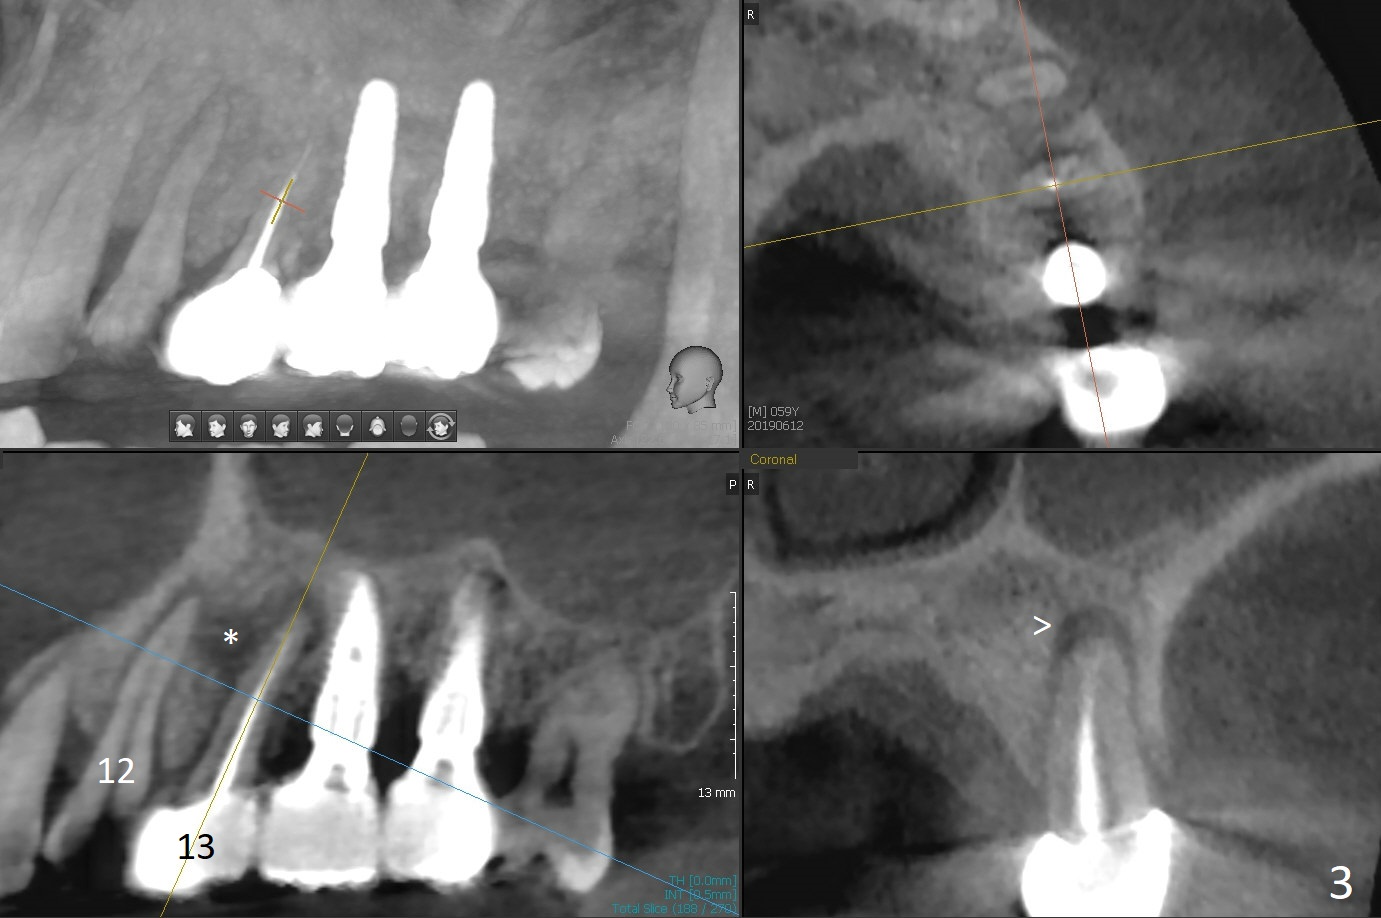

A 59-year-old man requests implant at #2 after those at #5, 14/15, and 29 (Fig.1). Sinus lift is required at #2 (Fig.2). Prepare PRF and SM implant (to be consistent with the previous ones without screw loosening). Although there is periapical radiolucency at #13 (Fig.3 >), there is another between #12 and 13 (Fig.3 *), which may be related to the apical infection at #12 (Fig.4 <).